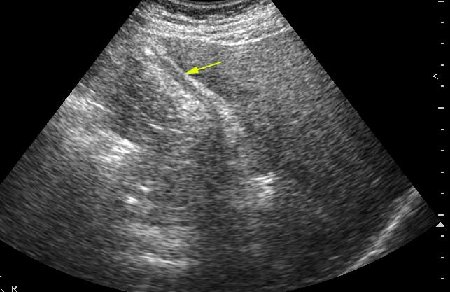

Похожий случай. Молодой мужчина, врач, длительные терпимые боли в правом подреберье.

2.По второму случаю можно было бы просто подумать о гиперкинезии ж.пузыря,который сокращается и "от глотка слюны".Но,прочитав эту фразу:"In patients with hilar cholangiocarcinoma and complete obstruction of both rigt and left hepatic ducts,extrahepatic bile ducts and the gollbladder appear empty(colapsed)",учитывая сложность выявления "малых" опухолей печени методом УЗИ,я думаю,что надо сделать КТ.